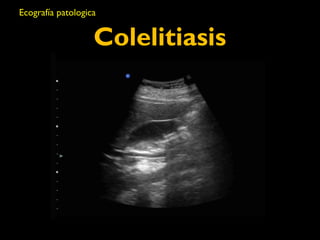

Colelitiasis

Ecografía patologica

Ecografia patologica